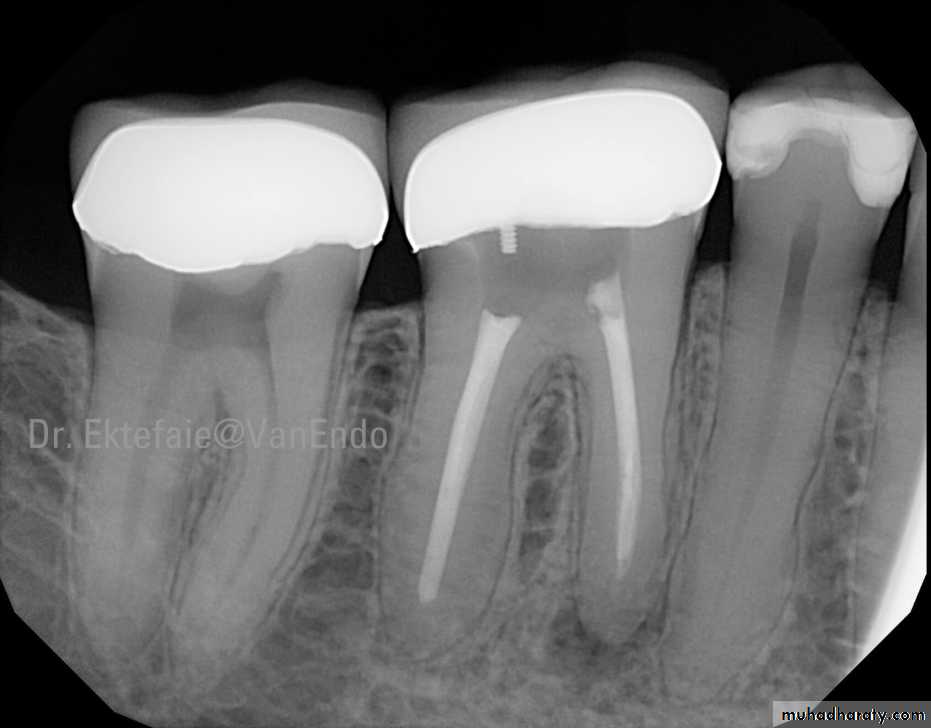

Electronic apex locatos (EAL)No. 20

Electronic apex locators (EAL) are used for determining working length as an adjunct to radiography. They are basically used to locate the apical constriction or cementodentinal junction or the apical foramen, and not the radiographic apex.No. 21

Components of Electronic Apex Locators• Lip clip• File clip• Electronic device• Cord which connects above three parts.No. 22

With apex locator the working length is determined by comparing the electrical resistance of the periodontal membrane with that of gingiva surrounding the tooth, both of which should be similar

A probe , such as a file, is attached to an electronic instrument with an electric cord and is inserted through the root canal until it contacts the surrounding PDL.

When the probe touches the soft tissues of the PDL, the electrical resistance gauges for both gingiva and PDL would have similar readings.

By measuring the depth of insertion

of the probe, one may determine the

working length of root canal